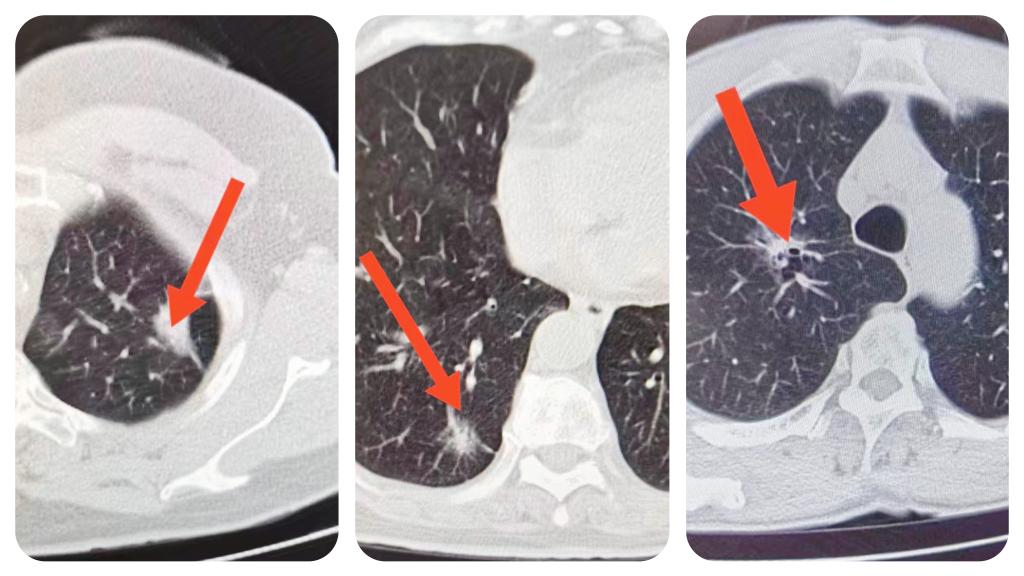

此次参与义诊的医务人员70余人,并配备先进的移动筛查车、车载CT等先进检测设备,义诊群众2000余人。4天内为782名群众完成了肺癌筛查,共筛查出220余例肺小结节,高危结节30例,高度疑似肺癌15例,心脏等彩超检查完成240余例。

此次义诊为广大市民提供“零距离,零费用”的优质医疗服务。在影像科技师人员操作完善检查后,迅速通过智能AI读片和5G技术快速传送影像数据到影像云,影像科诊断医师现场进行检测报告,以及给出初步诊疗意见,真正体现出了时效性。与此同时,功能科(彩超室)医生还免费为群众进行现场心脏等部位检查,如发现问题当场可咨询呼吸科、肿瘤科、肿瘤放疗科、疼痛科、血管介入外科、心脏外科等专家团队,除此之外,专家们还现场为各群众疾病问诊和健康查体,并进行宣讲保健知识,提出合理饮食、适量运动等建议,让群众在家门口享受到省市级优质的医疗服务,获得一致的肯定和广泛的赞扬。